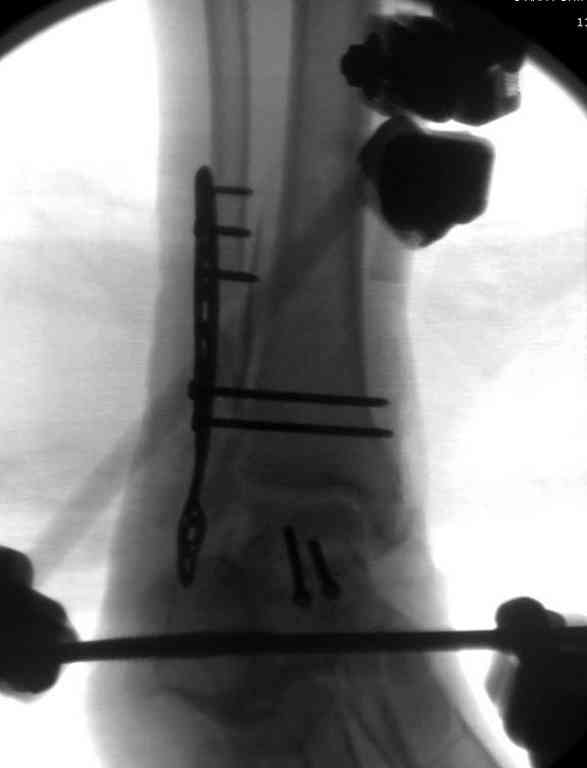

Второй случай прооперирован вчера.

10 дней назад поступил с открытым повреждением медиальной лодыжки и переломо вывихом таранной кости. Ургентно сделана репозиция с наложением наружного фиксатора + Irrigation&Debridment.

Во время репозиции выявили повреждение заднего сухожилия м. тибиалис и задней большеберцовой артерии. Медиальную рану удалось закрыть частично и установлен вакуум.

Дважды провели Irrigation&Debridment с заменой вакуума.

Вчера провели фиксацию.

Из-за многооскольчатости дистальной части малоберцовой, где невозможно было провести фиксацию шурупами, перелом зафиксирован подпирающей пластиной, которая должна служить дополнением отсутствующей дистальной части малоберцовой (lateral cortex substitute).

Для стабильности два шурупа на синдесмоз.

Медиальную рану с приближенными краями продолжаем вакуумировать (KCI). Наружный фиксатор оставлен на пару недель, надеюсь, небольшая рана будет гранулировать и закроется без кожной пластики. Фиксация медиальной ложыжки не планируется.